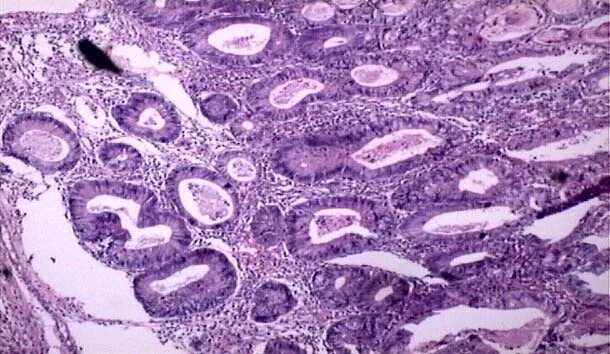

Высокодифференцированная аденокарцинома кишки